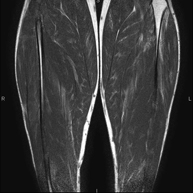

RM de Cama

RM de CamaExploració per estudiar lesions a tendons, a músculs i a nervis perifèrics. És de gran utilitat per diagnosticar ruptures fibrilars als bessons. La durada aproximada és de 18 minuts. No utilitza radiació ionitzant.